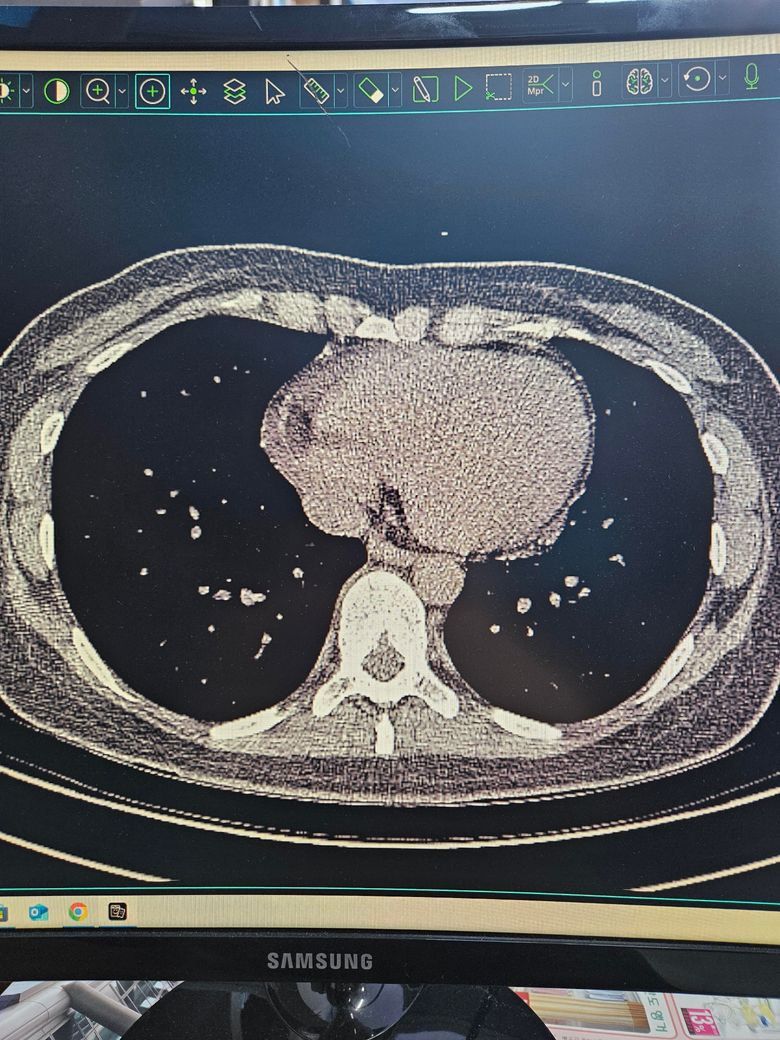

결핵의심 ct 사진인데 정확한건가요

결핵의심같다고 ct검사했는데 결핵이맞을까요..

객담검사했는데 배양검사결과는 아직안나오고

도말검사 pcr 다 음성나왔어요 ㅜ

• 1번 째 사진

올리신 CT 사진 두 장을 놓고 결핵 여부를 판단할 수 없으며, 심지어 올리신 CT 사진들을 폐를 자세히 볼 수 있는 세팅으로 설정되어 있지도 않습니다. 결핵의 경우에 CT 검사에서 의심할 수 있는 여러가지 소견들이 있을 수 있긴 하지만 확진을 내리기 위해서는 추가적인 검사들이 필요합니다. 일단 도말검사, PCR 검사에서 음성이 나왔다면 다행이며 결핵이 아닐 가능성이 충분히 있어 보입니다.